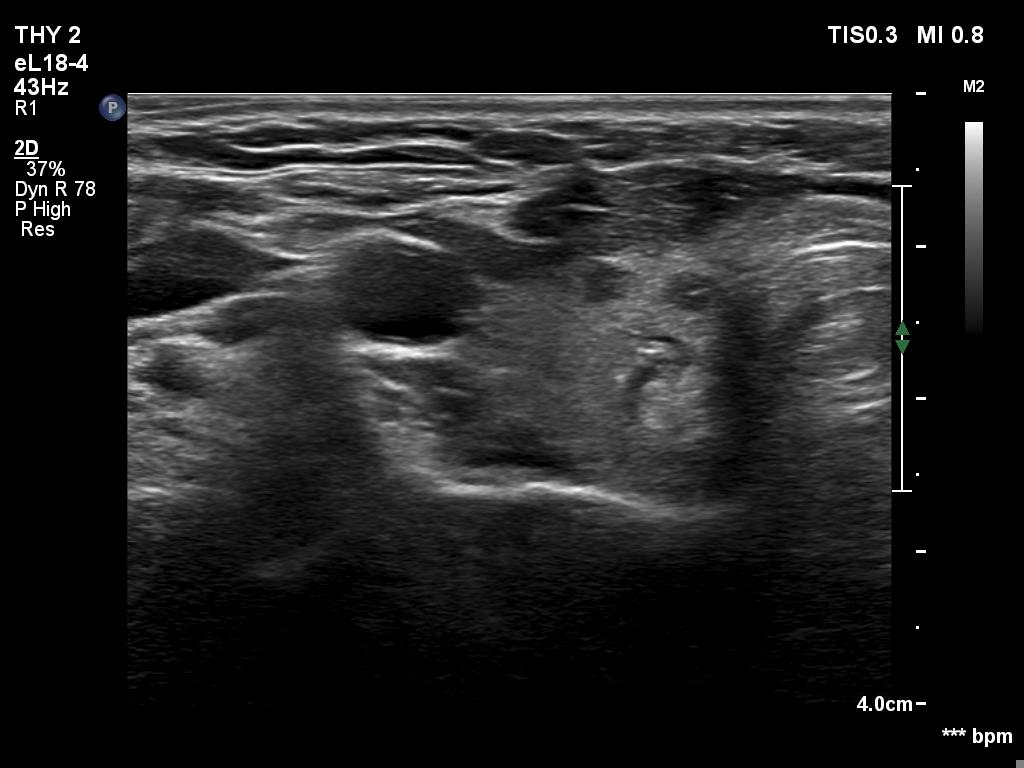

Second examination 6 month later (2nd row of images)

Clinical presentation. The patient was referred for evaluation of hyperparathyroidism. Elevated calcium and parathyroid hormone levels were found during the first evaluation. (These findings were not yet available when I first examined the patient.) Further evaluation disclosed a hyperfunctioning right lower parathyroid. The patient was operated on but no parathyroid tissue was found on histopathology. (A more experienced parathyroid surgeon was quarantined at the scheduled time of the operation, so a less experienced colleague performed the surgery.) Both hypercalcemia and hyperparathyroidism have persisted.

Laboratory tests: parathormone 129 pg/ml (normal value: 12-88), serum calcium 2,89 mM/L, phosphate 0,71 mM/L.

Ultrasonography revealed a hypoechoic mass corresponding to the right lower parathyroid.

Cytology resulted in benign lesion, a pattern which corresponded to a parathyroid adenoma.

The patient was reoperated and histopathology disclosed a parathyroid adenoma according to the right lower parathyroid.

If we compare the first and second ultrasound examination, it is evident that the ultrasound examination was not performed according to the rules of the profession at the first visit. (I will just mention that although in this case we only videotaped part of the entire study, we obviously overlooked the parathyroid gland under the right lobe. The reason for this is that we did not examine the part below the thyroid in the transverse section, and in the longitudinal section we started to examine the lower part of the thyroid too medially.)